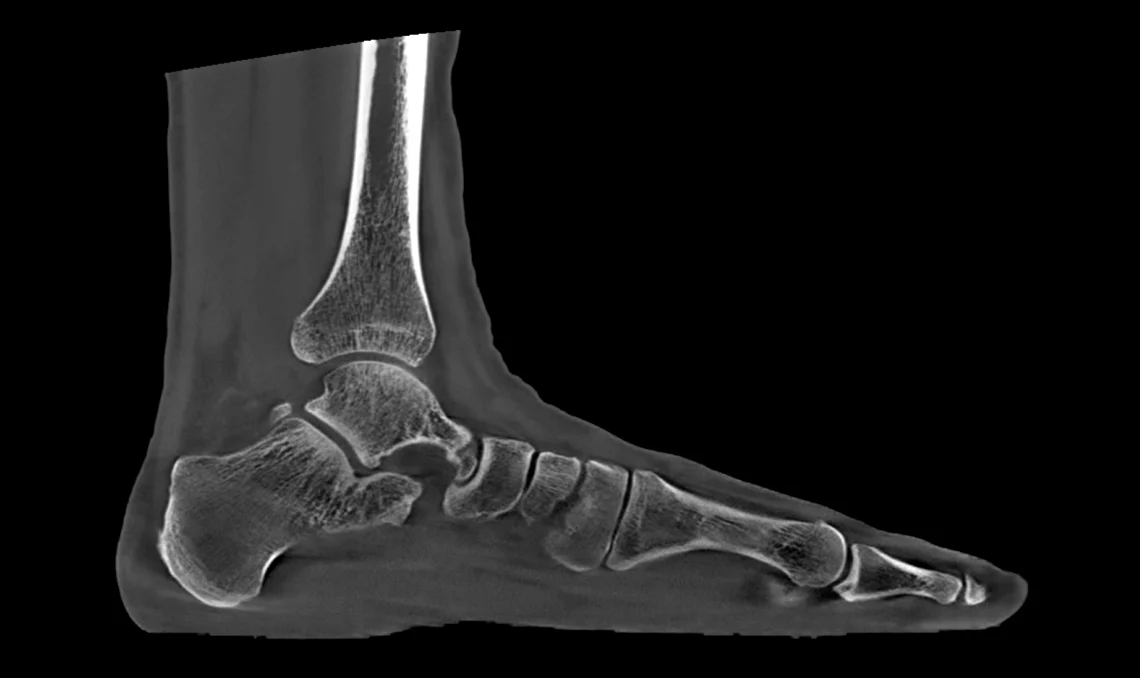

Le scanner CBCT Planmed XFI se distingue par une large ouverture de 85 cm et un champ de vision généreux, autorisant l’exploration du corps entier aussi bien en position allongée (décubitus) qu’en position debout (en charge). Son grand détecteur plan et sa source de rayons X haute puissance effectuent une rotation complète à 360° autour de la zone examinée, capturant rapidement des images anatomiques 3D détaillées.

Le système délivre des images 3D en ultra-haute résolution pouvant atteindre 75 microns, garantissant une qualité d’image exceptionnelle, une grande finesse de détail et une précision diagnostique optimale.